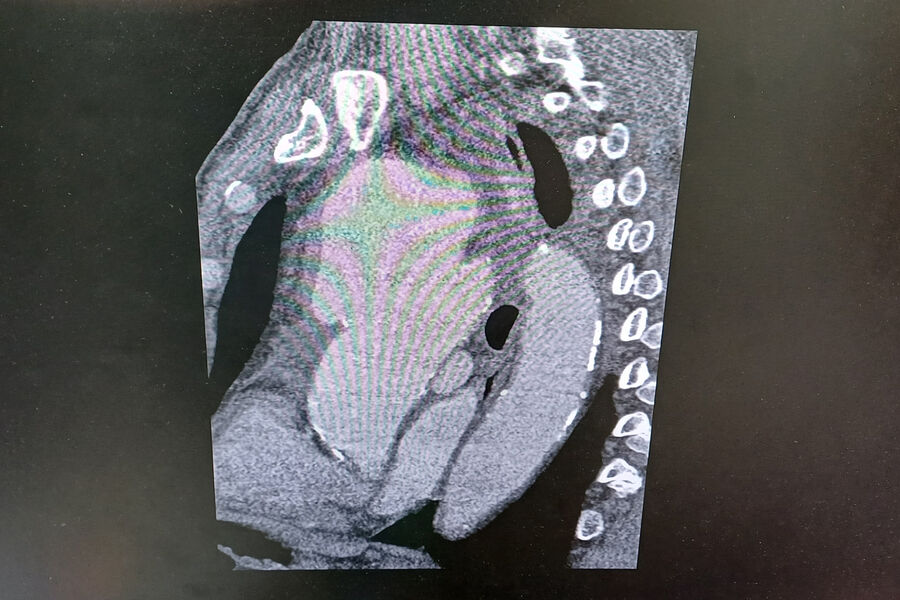

«Компьютерная томограмма подтвердила выпячивание аорты размером 9 на 9 сантиметров. Гигантская мешотчатая аневризма, больше, чем гусиное яйцо», — рассказал заведующий отделением №5 Рязанского кардиодиспансера Сергей Загородний.

По словам специалиста, аневризма сдавливала все близлежащие органы и ткани: трахеи, бронхи, верхнюю полую вену.